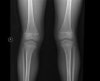

특히 나이가 좀 있으신 분들은 무릎 통증이 있어서 X-ray를 찍어보게 되면 대부분 관절에 X-ray상 퇴행성 변화가 와 있습니다.

관절에 생기는 퇴행성 변화는 나이가 들어서 생기는 당연한 결과입니다.

퇴행성 변화는 우리가 나이가 들면서 피부 노화가 오고 주름살이 생기고 피부가 처지는 것처럼 관절도 나이를 먹으면서 생기는 자연스러운 결과에 불과합니다.

따라서 중년 이상의 환자의 X-ray에서 관절에 퇴행성 변화가 보인다고 해서 그것이 통증의 원인이라고 단정지어서는 안됩니다.

관절 간격이 좁아졌다든지 뼈에 골극(spur)이 생기는 것은 나이든 사람이면 누구나 충분히 있을 수 있는 것입니다.

물론 소수의 경우 관절의 퇴행성 변화가 너무 심하여 관절 자체로 인한 통증도 있을 수는 있지만 대부분의 경우는 그렇지 않습니다.

많은 환자들이 X-ray에서 퇴행성 변화가 보인다는 이유만으로 관절염 진단을 받고 있습니다.